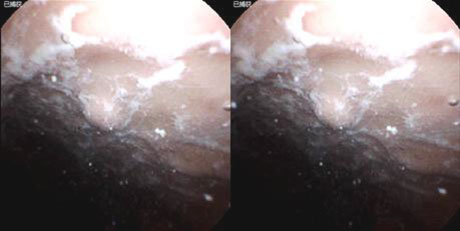

6、 克罗恩病

30岁,男性,腹痛、腹泻,胶囊内镜示克罗恩病。